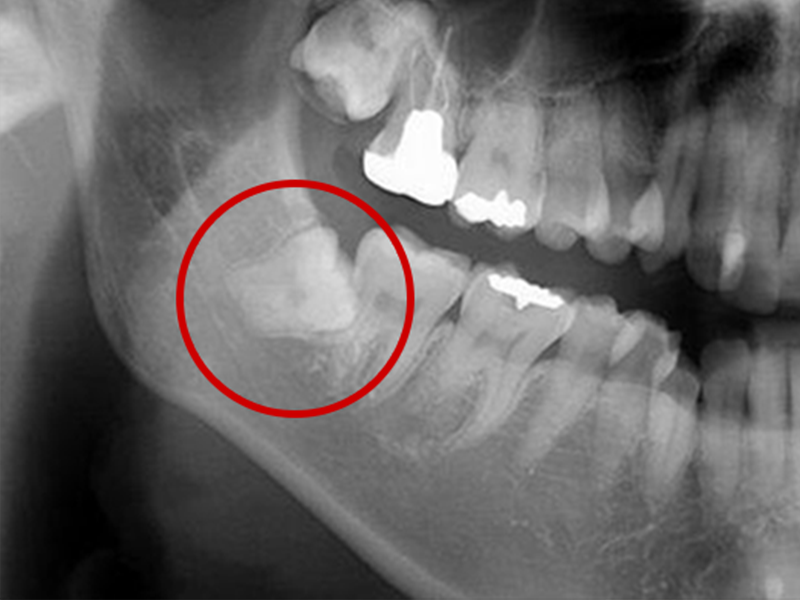

親知らずとは大臼歯(大人の奥歯)の中で一番後ろに位置する第3大臼歯です。

智歯とも呼ばれ20歳前後で生えてくることが多く、一般的には上アゴの左右2本と下アゴの左右2本の計4本ありますが、もともと親知らずのない人や4本そろっていない人など、個人差があります。

〈親知らずによる痛みの原因〉

親知らずは横や斜めに生えてきたり、歯ぐきがかぶっていることがあります。そのため親知らずの周囲には細菌が残りやすく、トラブルを起こし、痛みの原因になります。

親知らずが周囲に以下のような悪影響をもたらしている場合は、早めの抜歯をおすすめします。